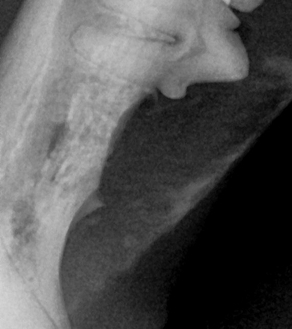

BEFORE

AFTER